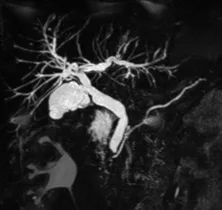

Figure 1. Patient exploré par bili-IRM pour une suspicion de migration lithiasique.

A. Cette coupe de bili-IRM 2D montre de multiples lithiases vésiculaires, ainsi qu’un calcul du bas cholédoque (tête de flèche).

B. Sur cette projection cholangiographique « MIP » issue d’une acquisition 3D en coupes fines, le calcul cholédocien est trop

petit au sein de cette VBP dilatée, et il n’est pas correctement visualisé. En cas de bili-IRM 3D, l’analyse de chacune des coupes

fines du volume est impérative. Ainsi, contrairement à la projection « MIP », la coupe fine passant par le cholédoque permet

de bien montrer le calcul (C)